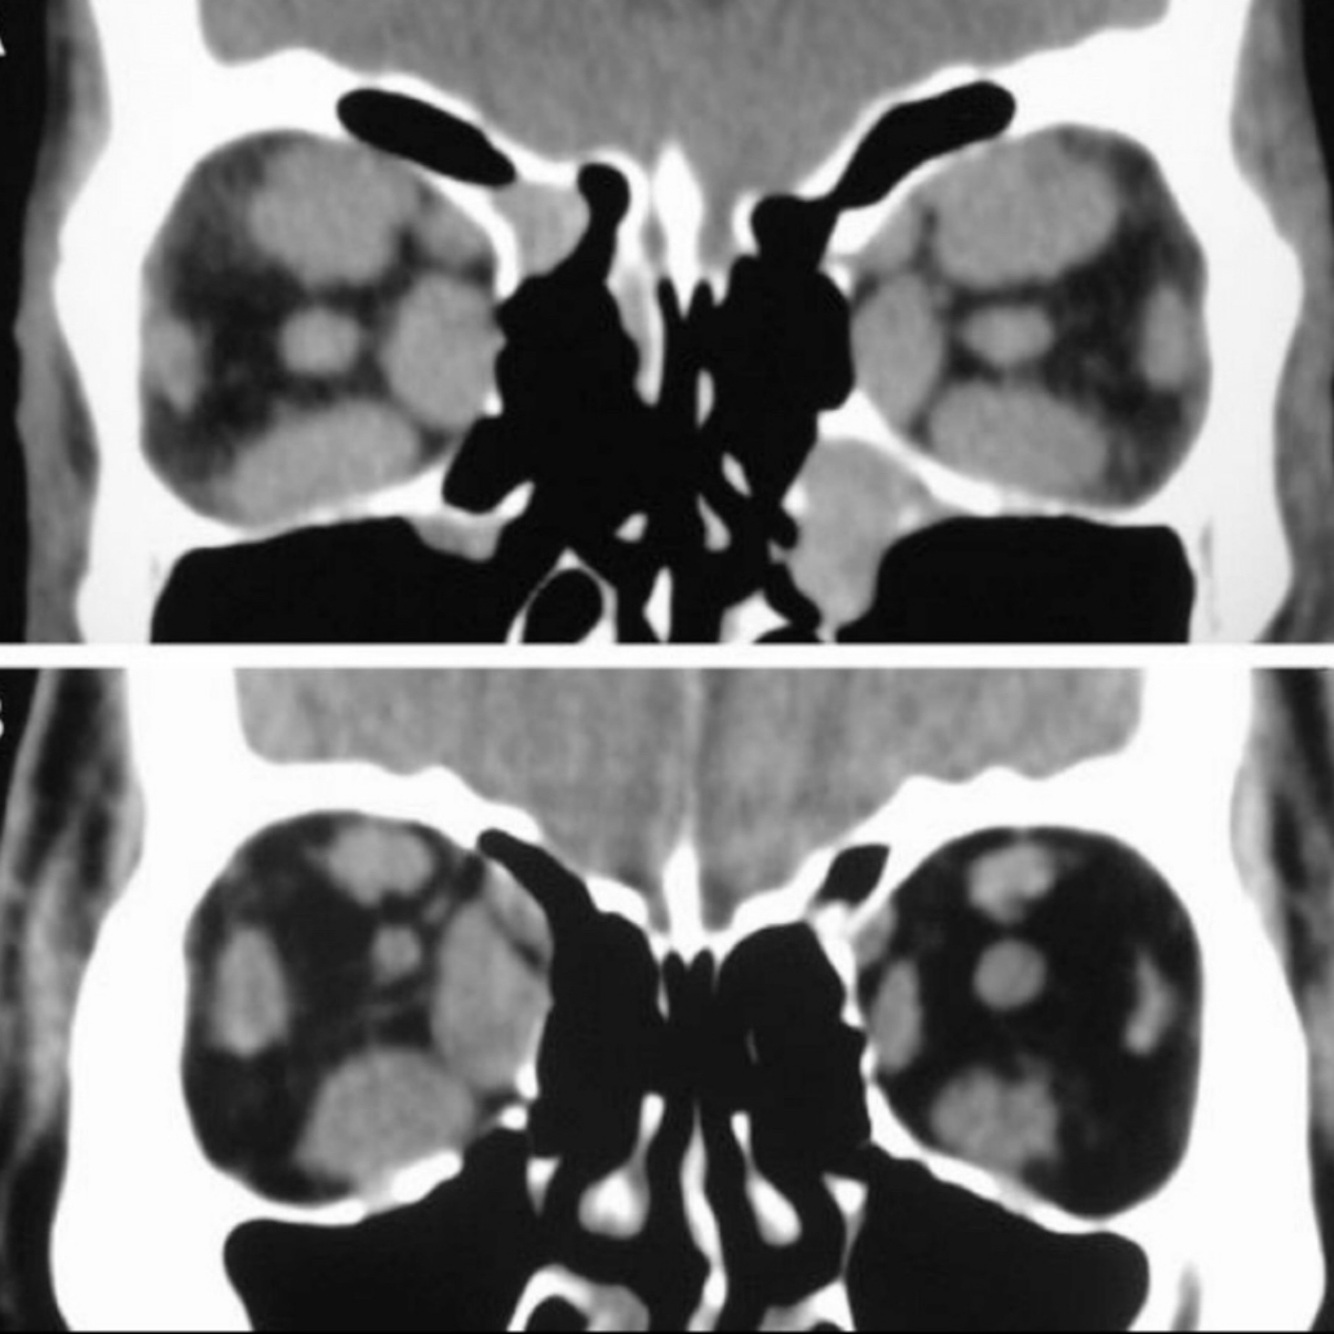

Hallazgos de TC de RB:

A

• Calcificación manchada o punteada

• Masa con densidad intermedia

• Capta contraste

Retinoblastoma subtipos:

• Bilateral

.

• Trilateral: + t. pineal